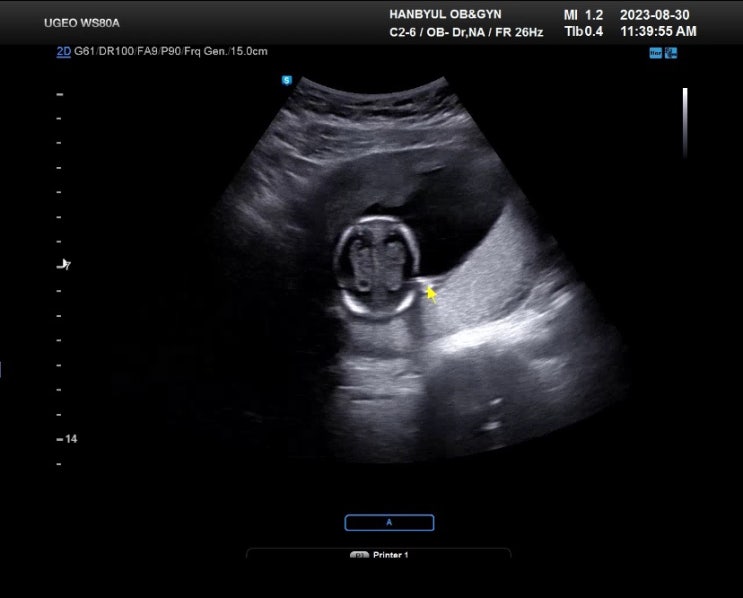

12주~16주간의 기록/2차 기형아검사, 성별확인, 전주 보건소 철분제

12주 ~ 15주 아직도 설사하던 시기 탈수 올 정도는 아님 과일,유제품,기름진 음식 피해야함 15주 6일 2차 ...